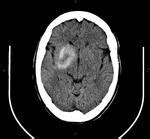

图像中心的白色部分即是造影剂外渗

造影剂外渗的影像学表现为梗死灶内或脑表面出现高密度影,形态和密度均和脑出血类似,类似于高血压脑出血或蛛网膜下腔出血表现,脑血管介入手术最担心的并发症就是血管破裂出血,所以术后通常都会复查头CT,在CT上如何区分脑脊液渗出和脑出血呢?

造影剂外渗与脑出血在以下四个方面区别

1.无占位效应;

2.外渗周围无水肿;

3.4h、24h 内复查头颅CT可见高密度影可明显吸收或完全吸收;

4.CT 值 60~95HU,局部达 150HU。

总之,颅内血管造影剂外渗常常出现在介入手术术后,外渗原因主要是因为颅内的血脑屏障功能被破坏,加之局部造影剂增加,渗透压增高,从而导致造影剂外渗。造影剂外渗在影像学上和脑出血非常相似,造影剂外渗无占位效应,周围无水肿,吸收快,CT 值 60~95HU,局部可达 150HU。另外,如果出现类似于蛛网膜下腔出血表现的造影剂外渗,其主要特点是常为对称分布,而蛛网膜下腔出血常常是不对称的。